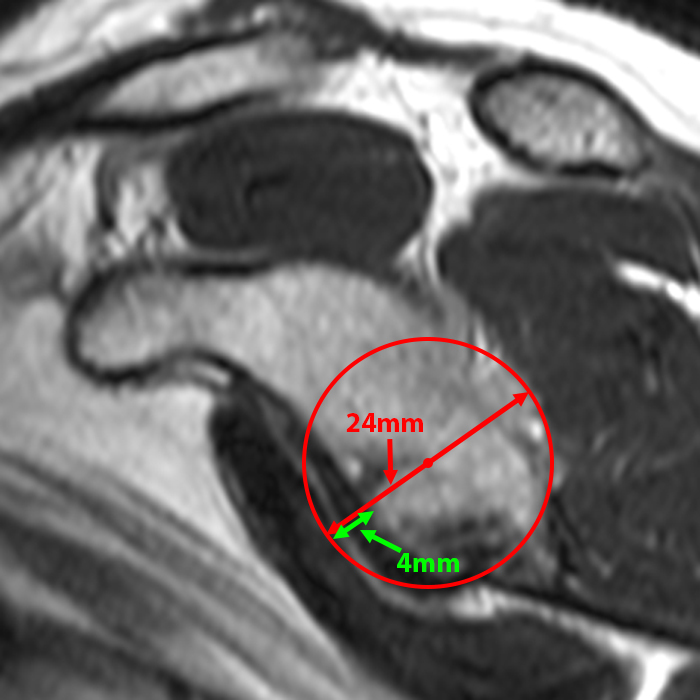

| L'immagine sagittale pesata in T2 con storia di lussazioni multiple della spalla mostra la glenoide en face. La larghezza della glenoide intatta misura 24 mm. La perdita ossea anteriore misura 4 mm. La traccia glenoidea misura quindi 0,83 x 24 - 4 = 15,9 mm | L'immagine assiale pesata in densità protonica nello stesso paziente dimostra la misurazione dell'intervallo di Hill-Sachs dal bordo mediale della lesione di Hill-Sachs (freccia) al bordo dell'inserimento della cuffia (punta di freccia). L'intervallo misura 23 mm, indicando una lesione fuori linea (off-track). |